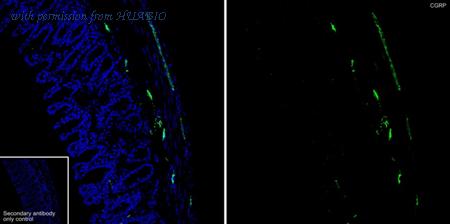

Application: IF-Tissue Species: Human Site: thyroid Sample: Paraffin-embedded section Antibody concentration: 1/1,000

Immunofluorescence analysis of frozen mouse colon tissue with Rat anti-CGRP antibody (HA610263) at 1/500 dilution. The section was not undergone antigen retrieval. The tissues were blocked in 10% negative goat serum for 1 hour at room temperature, washed with PBS, and then probed with the primary antibody (HA610263, green) at 1/500 dilution overnight at 4 ℃, washed with PBS. Goat Anti-Rat IgG H&L (iFluor™ 488, HA1133) was used as the secondary antibody at 1/1,000 dilution. Nuclei were counterstained with DAPI (blue).